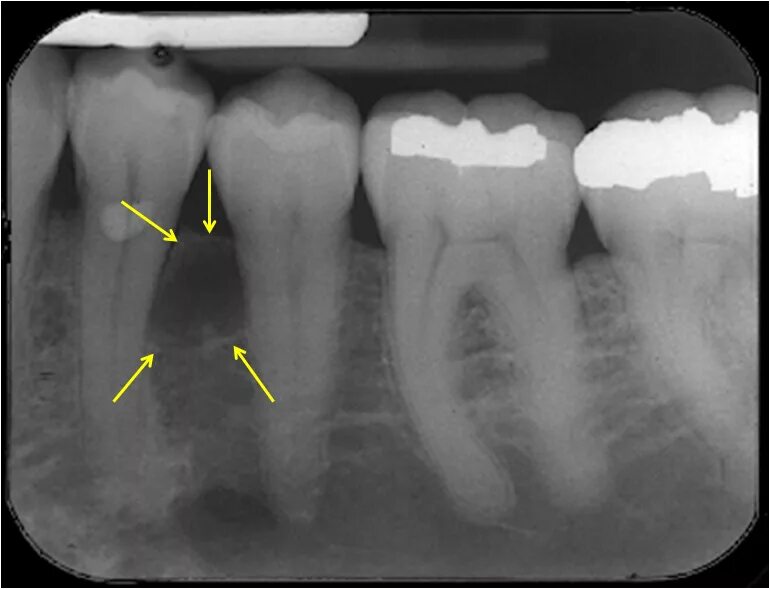

Матрица гаряева зубы и десна